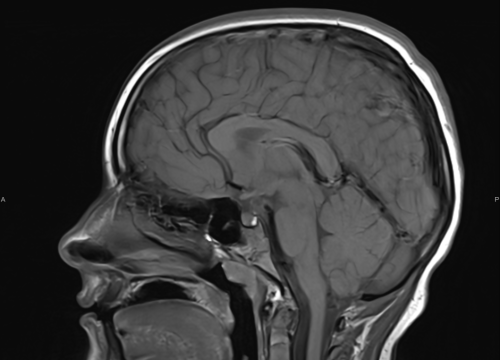

Ako su vam potrebni specijalistički pregledi mamografija, RTG, UZV, CT i MR, koji se inače koriste za dijagnostiku velikog broja zdravstvenih problema, možete ih obaviti već danas ili sutra.